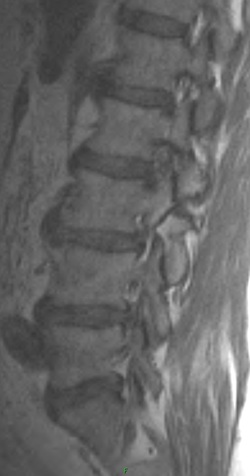

1. Aside from disc changes and spondylosis, what additional finding is present.

2. What are the types of spondylolisthesis? Pertaining to the anterolisthesis, which type does the patient have?